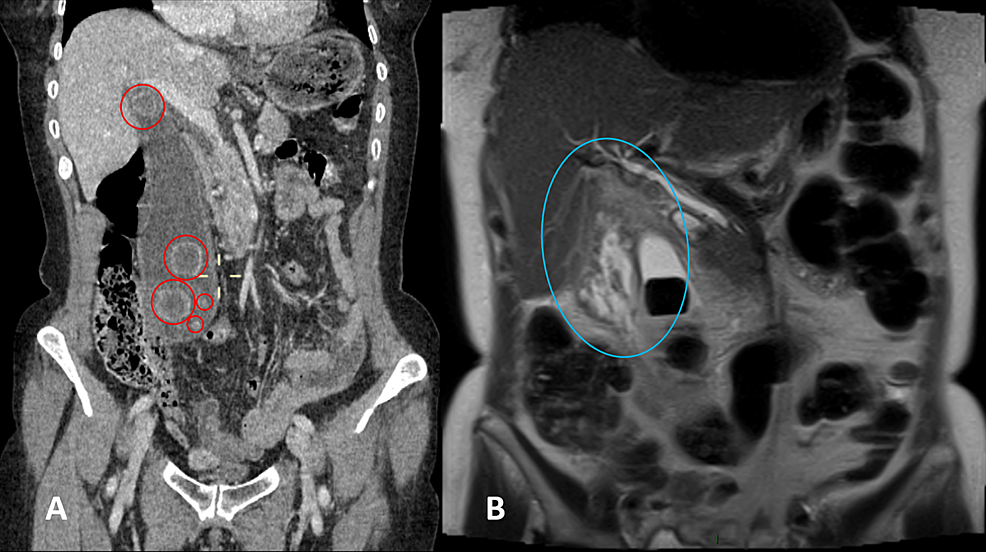

A 63-year-old woman presented with a two-day history of right-sided abdominal pain and swelling associated with dyspepsia. She had no history of jaundice. Abdominal examination revealed abdominal fullness on her right side with a palpable right iliac fossa mass. She was admitted for further examination. Blood tests showed high concentrations of inflammatory markers. She experienced an episode of pyrexia, requiring the commencement of intravenous (IV) antibiotics. A computed tomography (CT) scan of the abdomen demonstrated a markedly enlarged gallbladder (Figure 1). She was subsequently readmitted for an elective mini-laparoscopic cholecystectomy which was successful. Her postoperative recovery was unevenly and she was discharged at 24 hours postoperatively. A review at six weeks after discharge in the outpatient general surgery clinic was satisfactory.